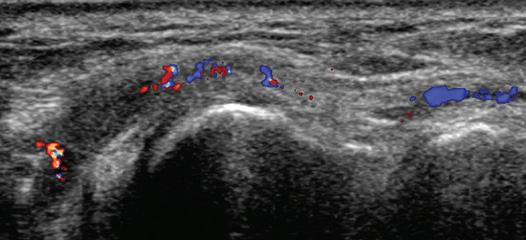

FIGURE 1.13 Anisotropy. Ultrasound images of anterior talofibular ligament in long axis (arrowheads) in the ankle show normal ligament hyperechogenicity (A) and hypoechoic anisotropy (open arrows) (B), when angling the transducer along the long axis of the ligament, thus aiding in identification of ligament relative to surrounding hyperechoic fat. F, Fibula; T, talus.